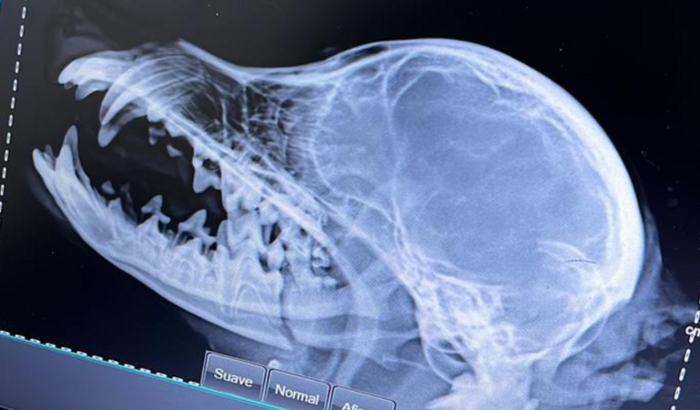

Oi pessoal eu sou a Anne Meireles tutora da Gaia, uma pincher 1 de apenas 4 meses e meio. Ela foi atacada por um cachorro maior e quebrou a parte inferior da mandíbula, por esse motivo ela não consegue comer e está sentindo muita dor. A cirurgia necessária custa 2200 reais, mas ela precisa ficar internada e fazer exames. Estou aqui pedindo a ajuda de vocês pois é um gasto muito inesperado e eu sou aluna bolsista não consigo custear esse gasto no momento 🙏🏽